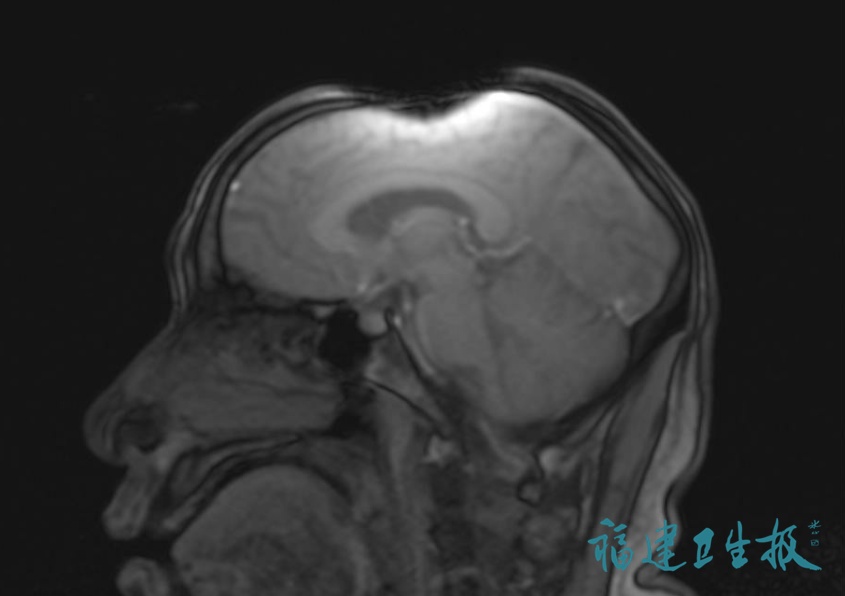

▲头发上金属异物导致的伪影